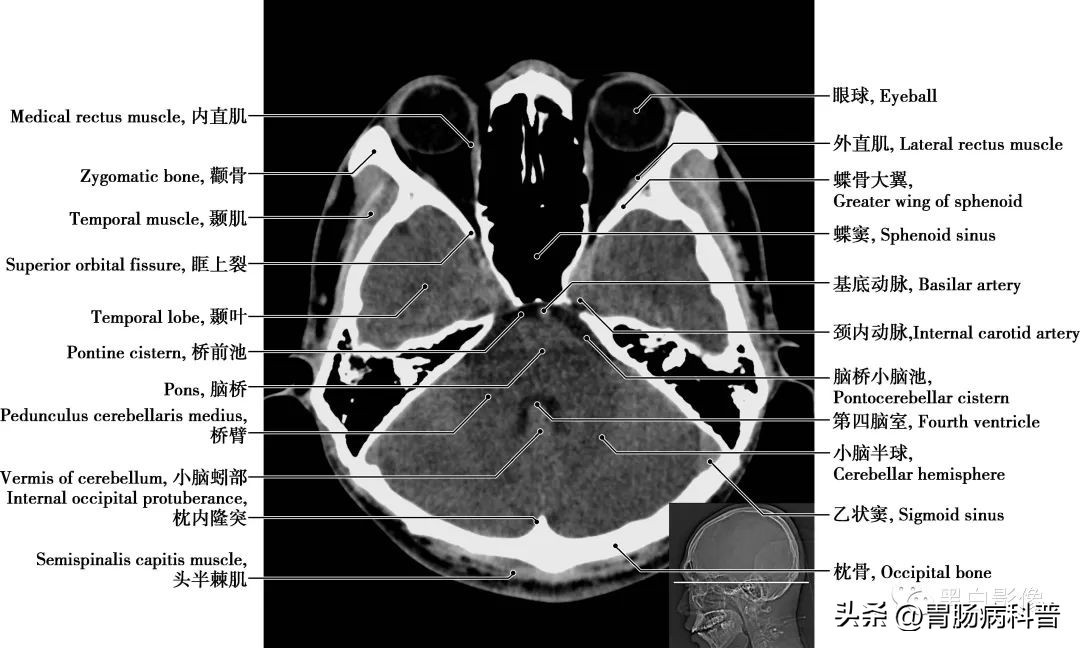

图1-1-12 经脑桥轴位切面

第四脑室 位于小脑、延髓和脑桥间,上接中脑导水管,下通脊髓中央管。接受第三脑室的脑脊液,并通过中孔或侧孔流向蛛网膜下腔,进入静脉系统。底部呈菱形,脑桥与延髓的神经核团多与此相毗邻。小脑半球 按功能可分为:前庭小脑,调整肌紧张,维持身体平衡;脊髓小脑,控制肌肉的张力和协调;大脑小脑,影响运动的起始、计划和协调

图1-1-14 经第四脑室中央轴位切面

脑桥 位于延髓上方,腹面膨大的部分为脑桥基底部,基底部向两侧变窄,称脑桥臂,与后方小脑相联系。基底部外侧有三叉神经出脑,横沟里由内向外依次有展神经、面神经和位听神经,有调整呼吸、调节肌肉运动等功能

图1-1-15 经第四脑室下部轴位切面

乙状窦 是两侧横窦前下方的延续,横窦离开小脑幕边缘以柔和的“S”形曲线形成乙状窦流入颈静脉球,乙状窦最后变成双侧颈内静脉而终止。颈内动脉 分为颅外段和颅内段,颅内段分为C 1 颈段、C 2 岩段、C 3 破裂(孔)段、C 4 海绵窦段、C 5 床段、C 6 眼段和C 7 交通段。分支分布于视器和脑